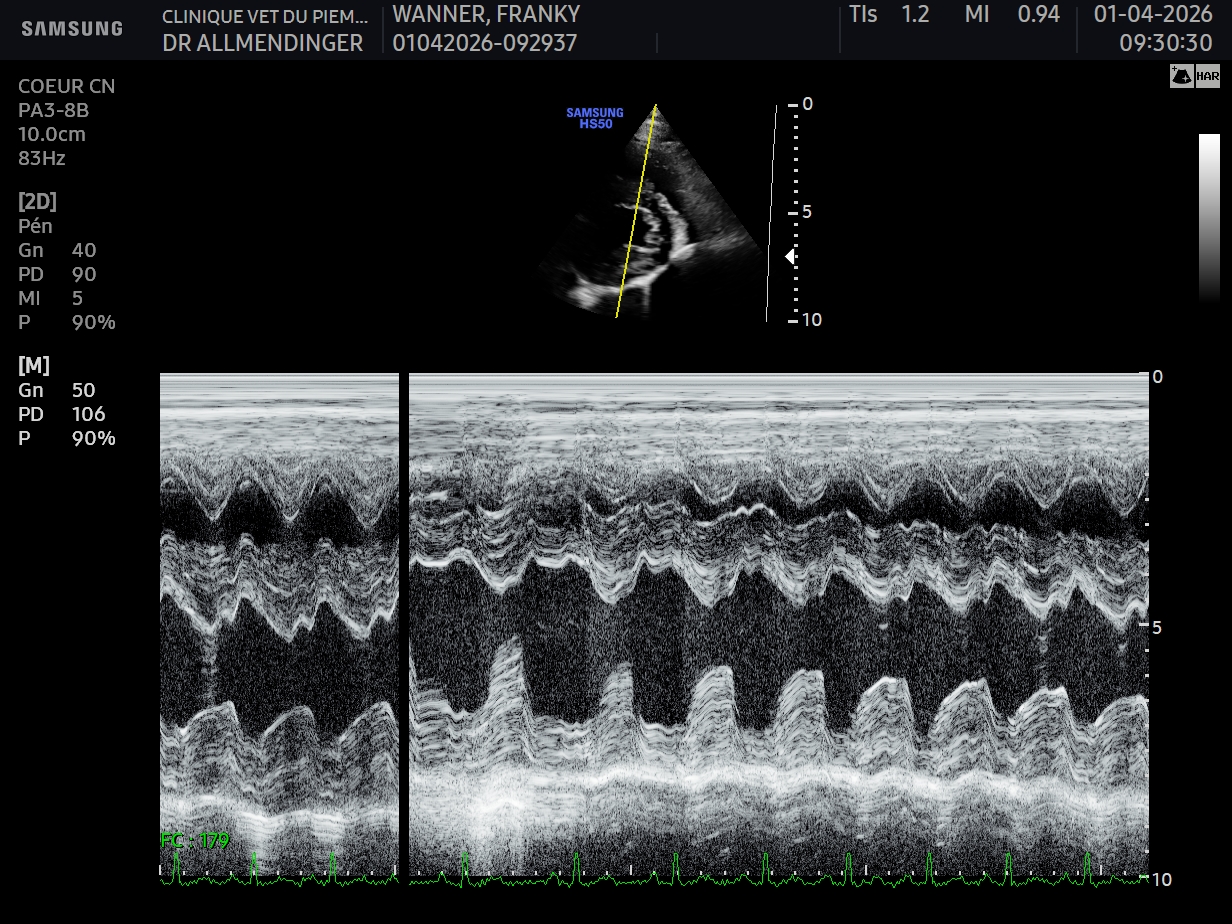

Geste technique : Mesure échographique du LA/Ao (rapport oreillette gauche/aorte)

- Connaître les principaux examens à considérer chez un chien présenté en dyspnée aigue

- Connaître les limites de l’examen échographique pour l’exploration d’une dyspnée aigue chez le chien

- Connaître les limites de l’examen sanguin (mesure BNP) pour l’exploration d’une dyspnée aigue chez le chien